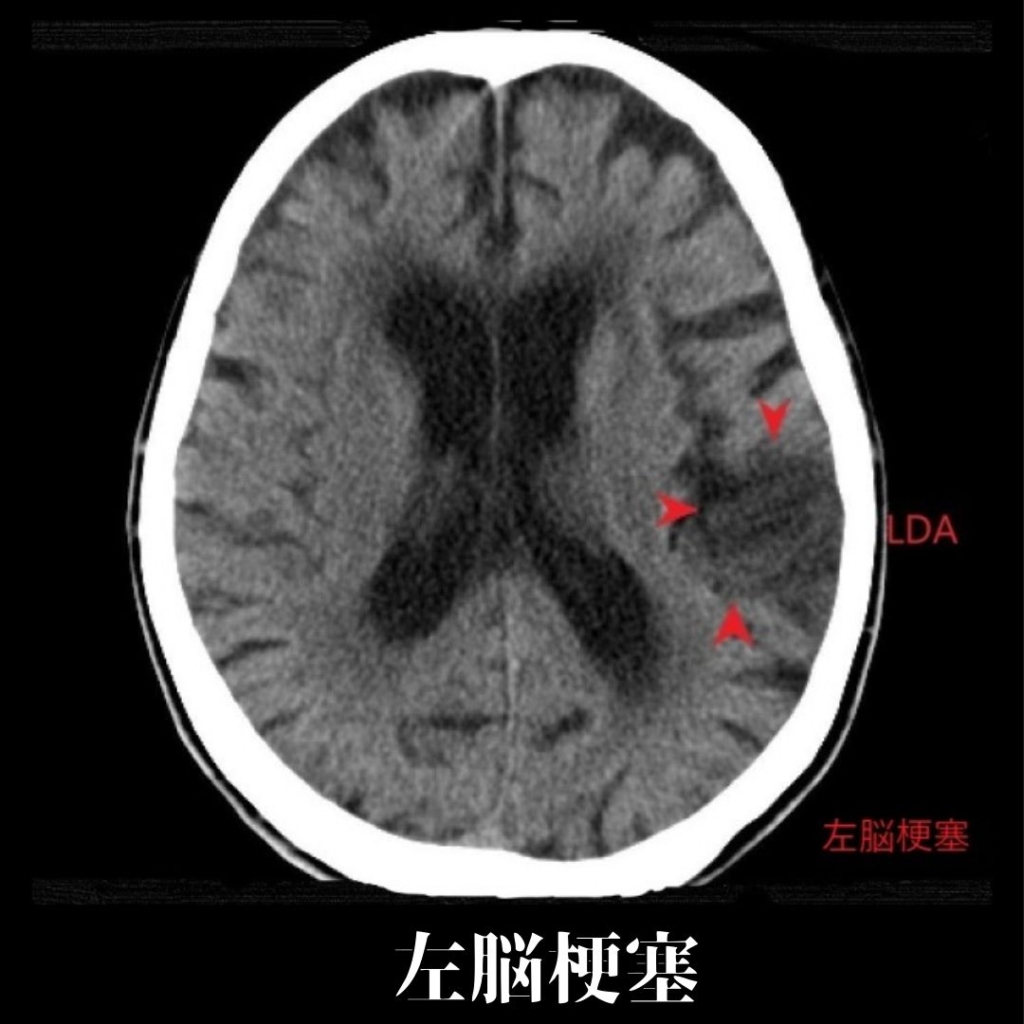

16列マルチスライスCTを完備

当院では、16列マルチスライスCTを完備しております。CTとは、Computed Tomographyの略で、X線を使って身体の断面を撮影することが可能な検査となります。短時間での検査ができ、多くの情報を得ることができます。

脳疾患(脳梗塞、脳出血ほか)、胸部疾患(肺気腫、気胸、肺腫瘍、肺がんほか)、腹部疾患(胃がん、大腸がん、すい臓がん、肝臓がんほか)、骨折等の整形外患ほか、多岐にわたる検査が可能です。